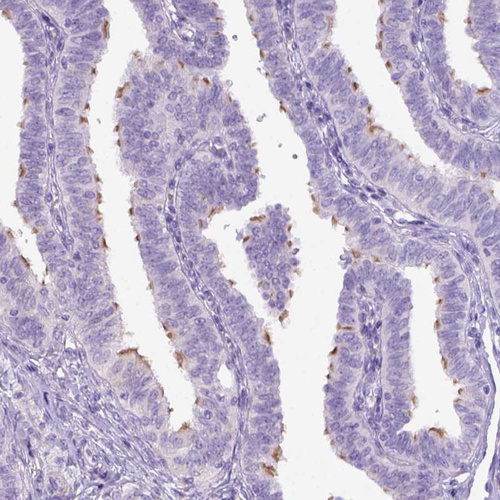

Immunohistochemical staining of human bronchus shows strong positivity in respiratory epithelial cells.